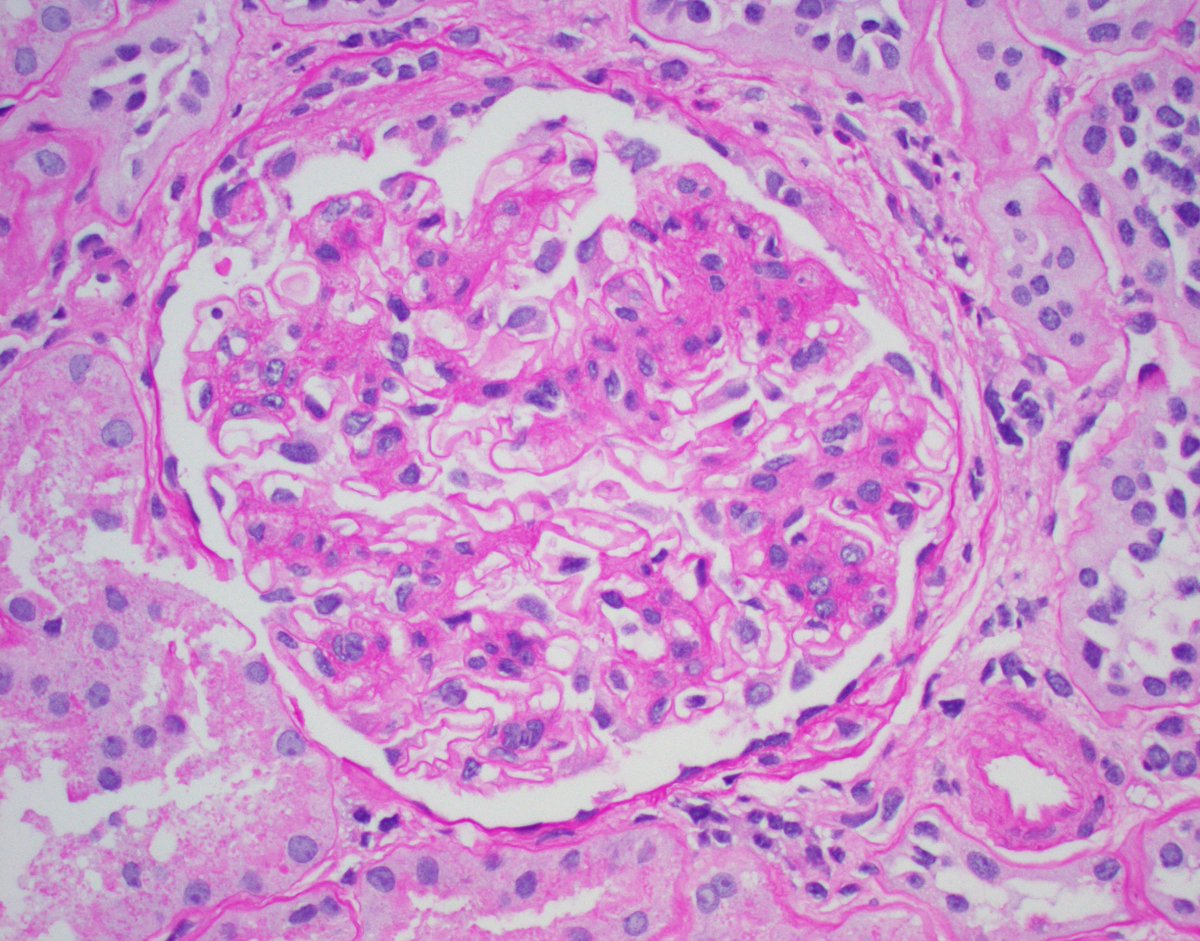

Unfortunate but not rare IgAN presentation. Pt in their 30's, no PMHx, presented with HTN emergency, CKD, hematuria, proteinuria. Advanced IgAN with severe IFTA, focal active crescents (M1 E1 S1 T2 C1). Wish we could catch these cases earlier. #renalpath #pathtwitter #nephrology